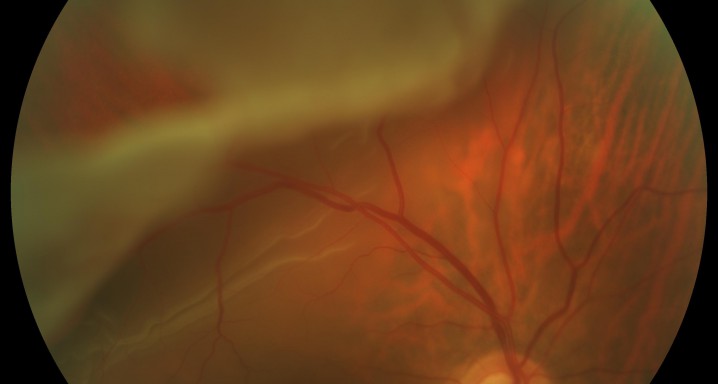

Este tratamiento se utiliza para el desprendimiento de retina y consiste en la colocación de una sonda que realiza una quemadura por congelación de tejidos endooculares. La criocoagulación se utiliza para tratar el desprendimiento de retina y tumores intraoculares, entre otros, pero hoy en día está prácticamente en desuso por el empleo de otras técnicas quirúrgicas más avanzadas.